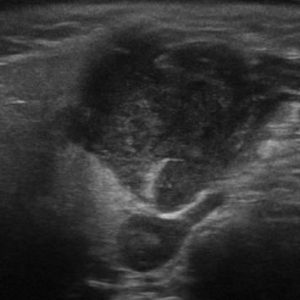

U tuyến nước bọt

Lượt xem: 138» 19-01-2021 -

U tuyến nước bọt

Lượt xem: 153» 19-01-2021 -

U tuyến nước bọt

Lượt xem: 131» 19-01-2021 -

U tuyến nước bọt

Lượt xem: 102» 19-01-2021 -

U tuyến nước bọt

Lượt xem: 146» 19-01-2021 -